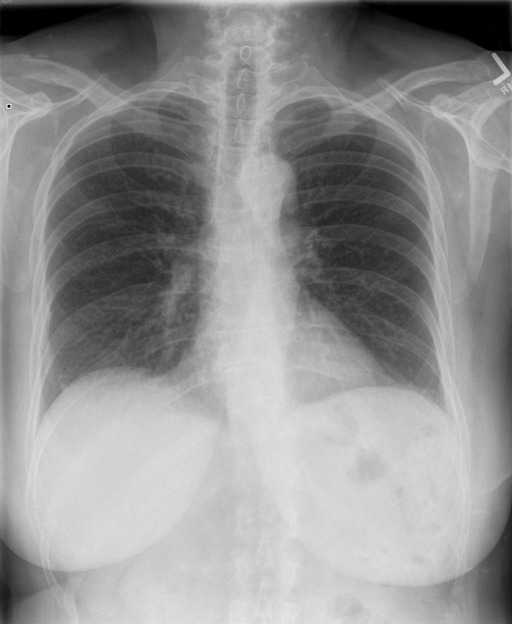

Comparison of CXAS to Human Anatomy Annotations on Real World Chest X-Rays

To test the real-world applicability of PAX-Ray++ for developing anatomy segmentation models, we prepare a test set of 30 frontal and lateral chest X-Rays each from the PadChest dataset [38] for a total fo 60 images. First, we use our best segmentation model based on the validation performance to generate preliminary anatomical segmentations. Then, we tasked two medical experts to independently examine and correct these densely annotated X-Rays using the annotation tool CVAT [39]. Even in this simplified annotation process, the expert denoted that a single image correction would take roughly 1.5 hours on average due to the sheer amount of considered classes.

We display qualitative results in Fig. 3. The annotators tend to be content with most annotations. There are edits at the extensions of the esophagus, trachea, and aorta and corrections of the lower ribs. There is little consensus for classes in the abdominal area, such as the stomach, as seen on the right of Fig. 3 . In contrast, the annotators often align for bone classes.

We show the quantitative segmentation performance against medical expert annotations for all classes in Fig. 3 . The dashed lines represent the IAA, whereas the dotted line displays the average MAA. As the task for the human annotators was not to annotate from scratch but to correct wrong pixel-wise predictions, we can see a high MAA for most classes. In the frontal view, the most significant disagreements exist for rare bone structures such as L3 and C4, lower ribs, the mediastinal distribution, or the breast tissue. The IAA and MAA are highly similar with mIoU of respective 95% and 94%. The Hausdorff distance for MAA is slightly lower than the IAA, indicating slight differences in boundary annotations while maintaining a considerable overlap with the other annotator. In the lateral view, the concrete delineation of rib structures appears ambiguous, leading to lower MAA and IAA with a greater IAA than MAA for all metrics in this supercategory. Overall there is less agreement between the medical experts in the lateral view, leading to a better average MAA than IAA across all metrics (i.e. 85% vs 83% mIoU). While the experts propose changes to the original predictions, they are often not overlapping. In the lateral view, rib segmentations can become quite hard to interpret. While both annotators disagree with the rib segmentations, they do not always agree on how they should look. Similarly to the frontal view, tube-like structures like the esophagus are extended as they can appear fractured at times.